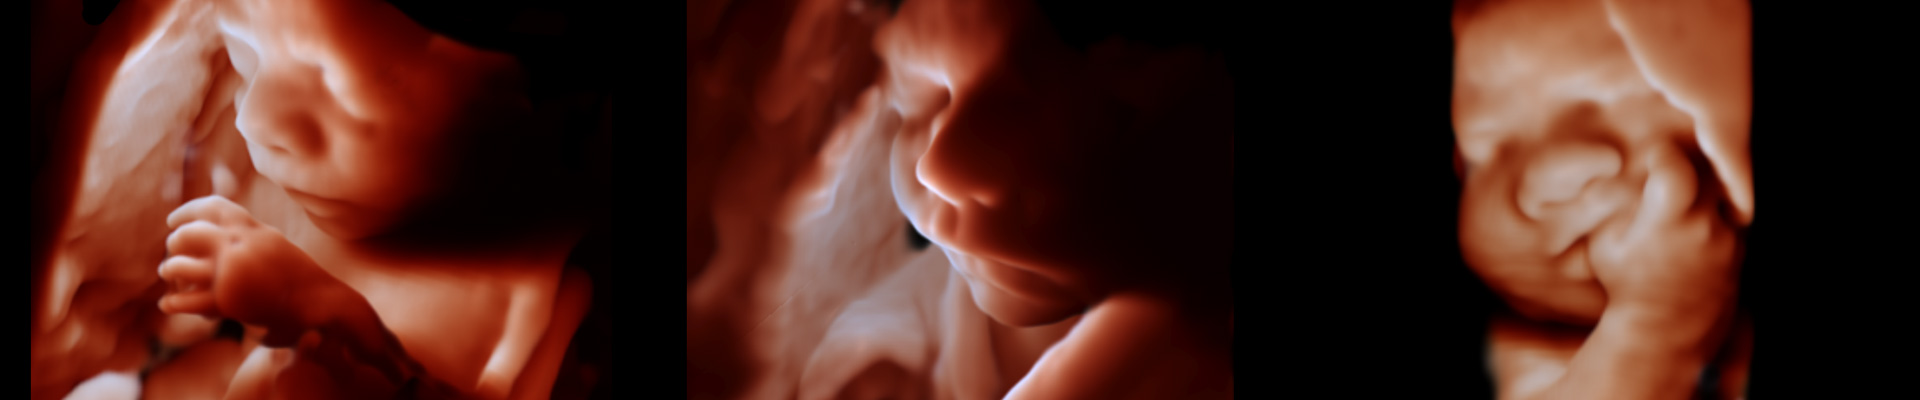

With the latest technology, we can provide detailed, photogenic images and videos of your baby, offering additional insights into their well-being. WSMI is proud to introduce the first 4D ultrasound in Fairfield LGA, featuring the cutting-edge EPIQ Philips system for the highest quality results. We provide top-notch care, with a specialist on-site to ensure expert attention every step of the way.

A 4D ultrasound is an advanced form of ultrasound that allows you to see your baby’s movements and gestures in real time, giving you a more immersive experience.